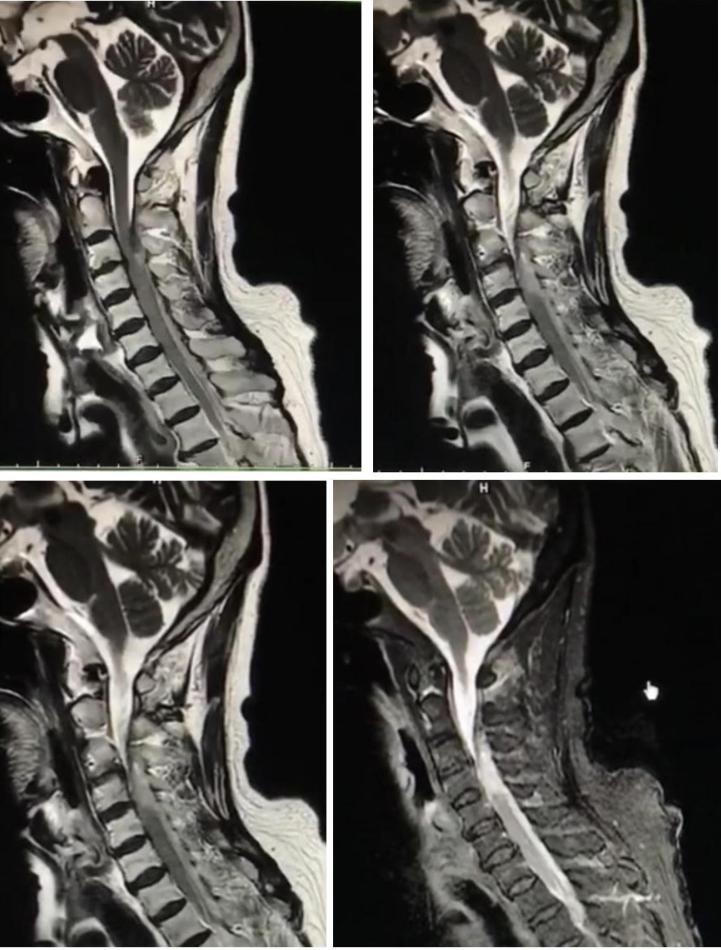

男性68岁,四肢末梢麻木2月余,伴有站立不稳,加重1周,不能独立行走。查体双侧跟膝胫试验欠稳准,双侧位置觉、震动觉减退。

答案:脊髓亚急性联合变性。患者老年男性,亚急性病程,以深感觉受累为主要表现,脊髓影像长节段病灶,轴位显示后索病灶“圆点征”,颅内影像改变无特异性,NMOSD相关抗体检测以及OB均阴性。其特征性影像有“圆点征”、“小字征”、“三角征”、“八字征”等。